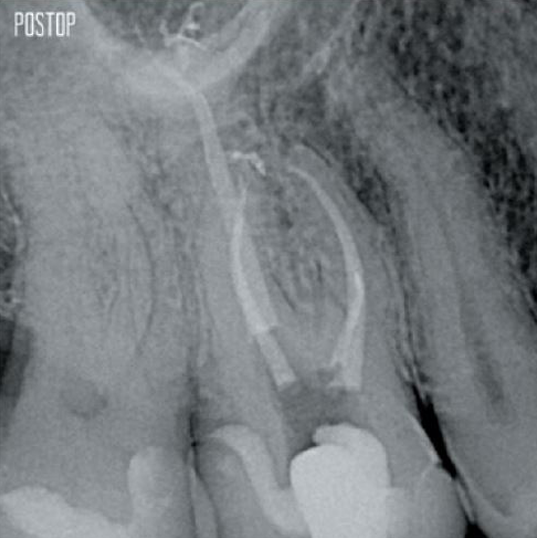

Photos courtesy of Dr. Ahmed Salman

More dentin preserved. Appropiate shaping, irrigation, and obturation ensured.

Successful root canal treatment starts with adequate access to the pulp chamber. The ideal procedure provides access to root canal orifices with minimal loss of dentin.

A Conservative Endodontic Cavity (CEC) is the recommended with the TruNatomy® system.

The union of the file geometry, regressive tapers and the slim, highly-flexible wire enables efficient root canal treatment while removing only dentin where clinically needed.1